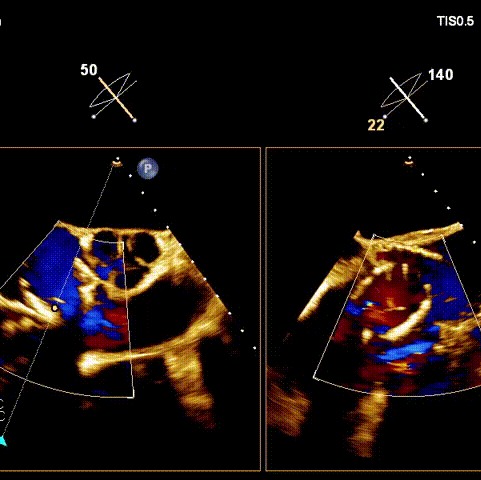

術(shù)后超聲

術(shù)前經(jīng)過全面系統(tǒng)的評估后,考慮患者存在高齡、心功能減低、三尖瓣瓣環(huán)重度擴(kuò)張(三尖瓣極重度反流)等高危因素,因此廈心結(jié)構(gòu)心團(tuán)隊(duì)聯(lián)合超聲心動、麻醉及護(hù)理團(tuán)隊(duì),制定了詳盡的圍術(shù)期治療方案及術(shù)中治療難點(diǎn)預(yù)案。術(shù)中,由王焱院長主刀,在蘇茂龍主任超聲心動團(tuán)隊(duì)的輔助,上海市第一人民醫(yī)院陸方林主任的協(xié)助下,僅用時30分鐘,即順利完成了三尖瓣原位置換的手術(shù)。術(shù)中患者血流動力學(xué)穩(wěn)定,術(shù)后即刻顯示LuX-Valve Plus瓣膜位置良好,固定穩(wěn)定,瓣膜功能正常,無瓣周漏。